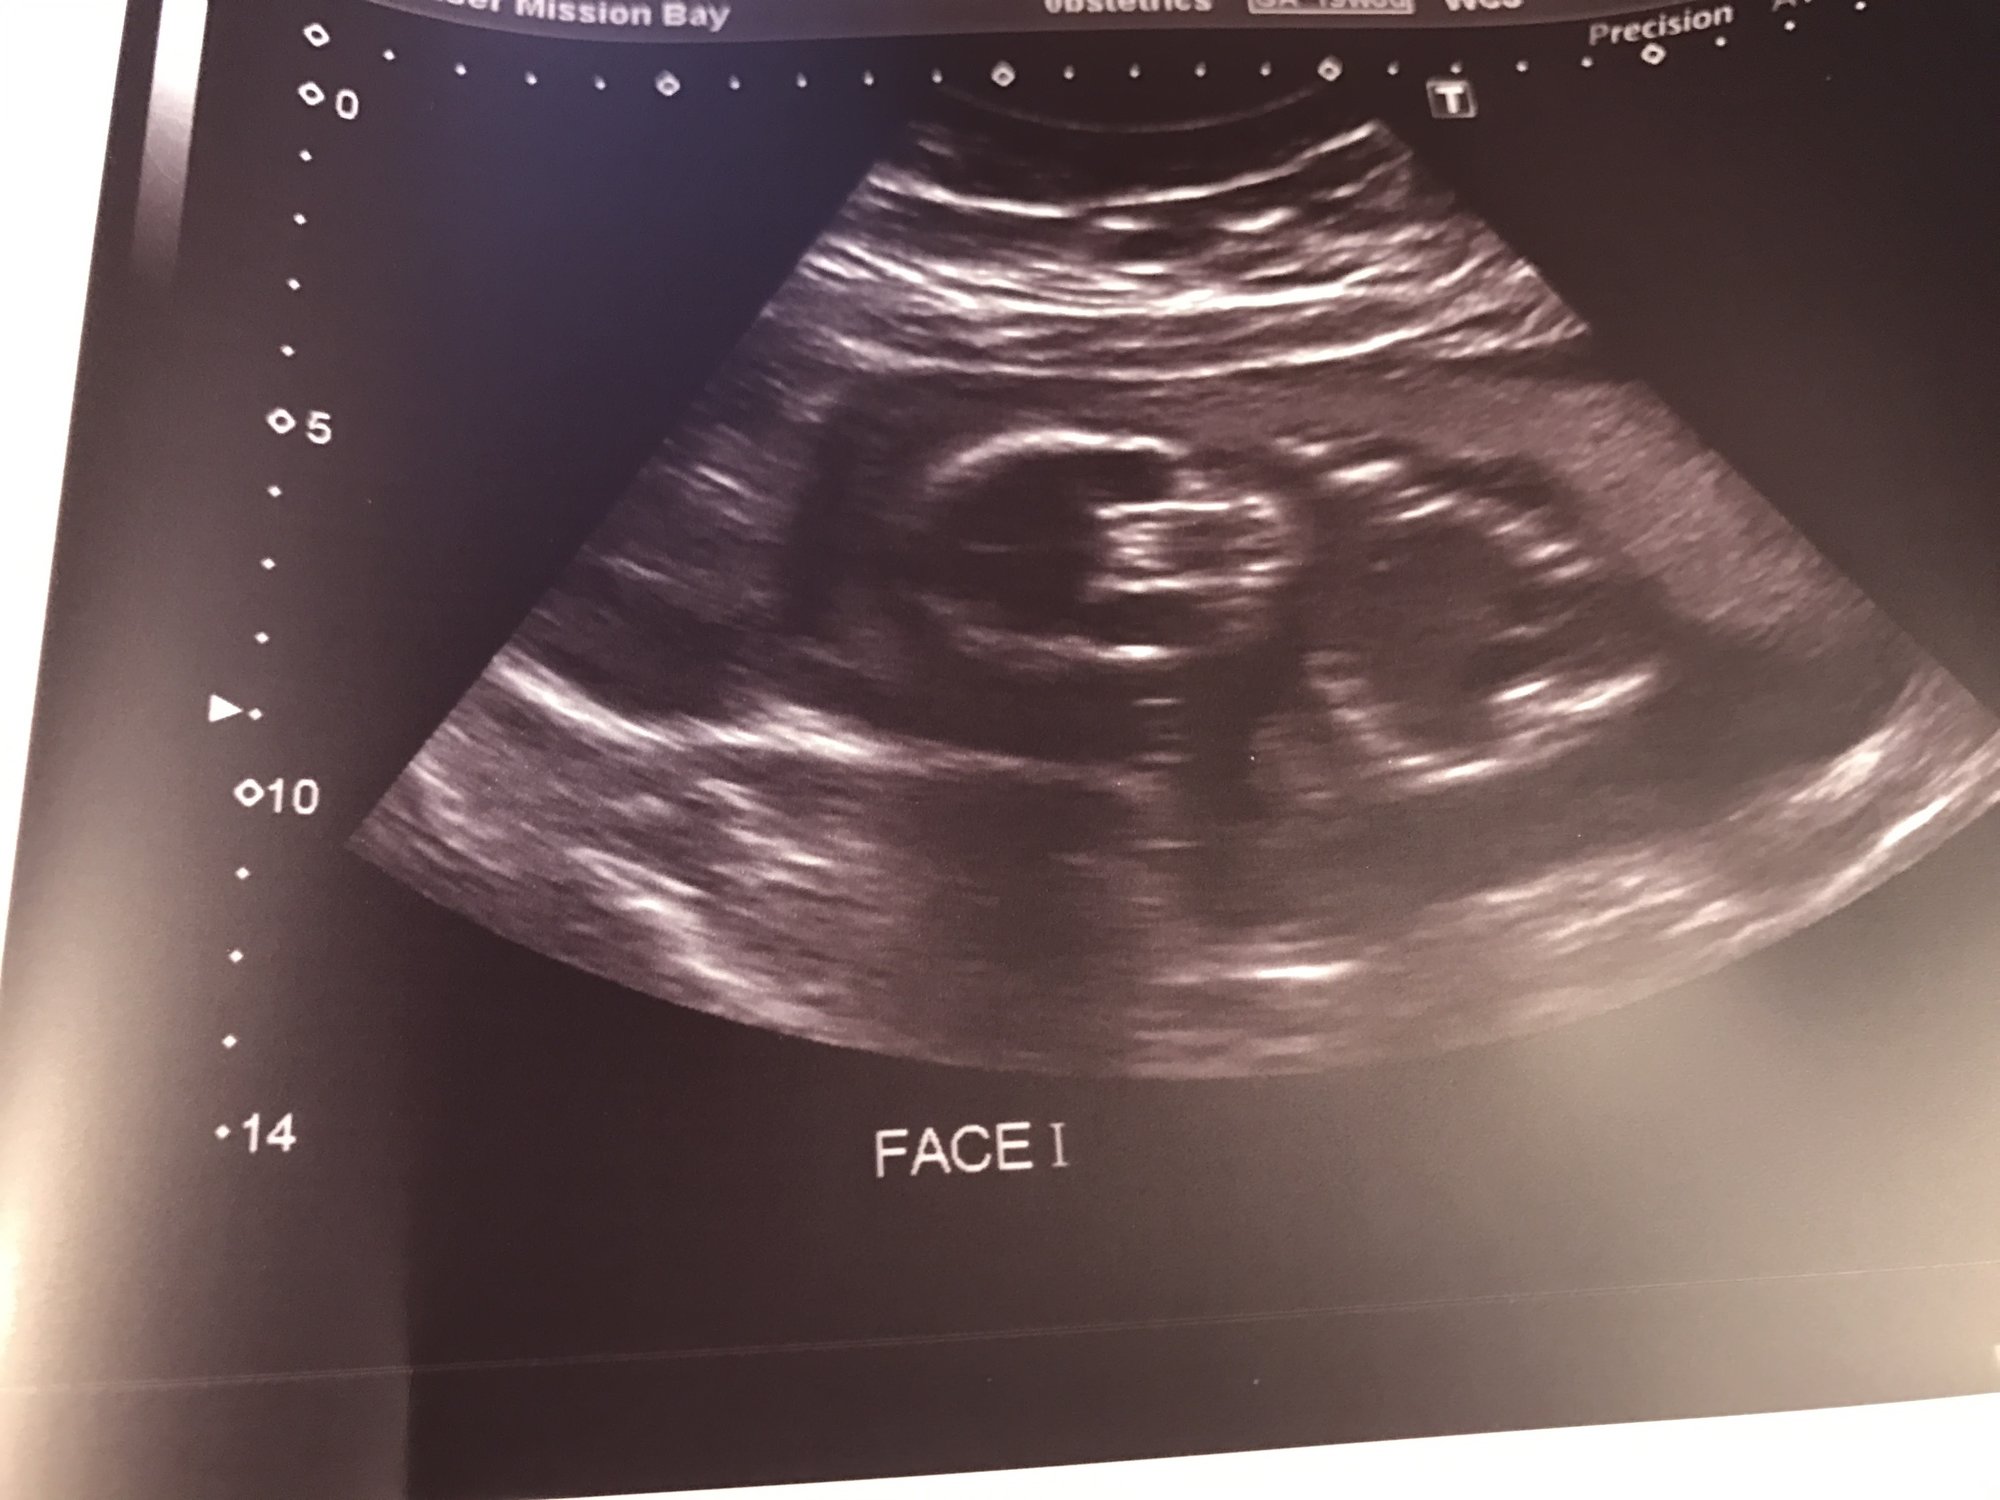

Not sure if this question goes here, but it didn't seem to fit anywhere else and I learned this at my anatomy scan: is anyone else carrying really low? I don't know if it was just baby's positioning durinf the scan, but the tech kept commenting on how low he was. She wasn't concerned, she just said everyone carries different. But she had the probe pretty low in my pelvic region to get a good image of his head.

A/S was great. May need to go back as she had trouble capturing a couple shots. We confirmed that he's a boy (boy parts!). The pic of his face/skeleton is kinda creepy. But just because it's a skeleton.